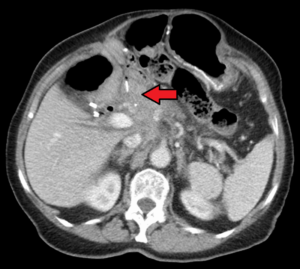

Pancreatic cancer is one of the most aggressive forms of cancers, often with a very poor prognosis. Approximately 11 out of 100,000 men and women per year die from pancreatic cancer in the United States. One of the drugs used in treating pancreatic cancer is nab-paclitaxel. This is a nanoparticle made up of albumin bound to the paclitaxel. It is currently the first line of treatment against pancreatic cancer.